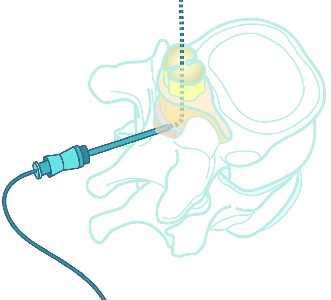

Detailreiche Fotografien aus der medizinischen Praxis ergänzen die Texte; moderne, genaue,

wissenschaftliche Zeichnungen geben Einblick in die Anatomie und die Funktion der Lunge und

anderer Organe.